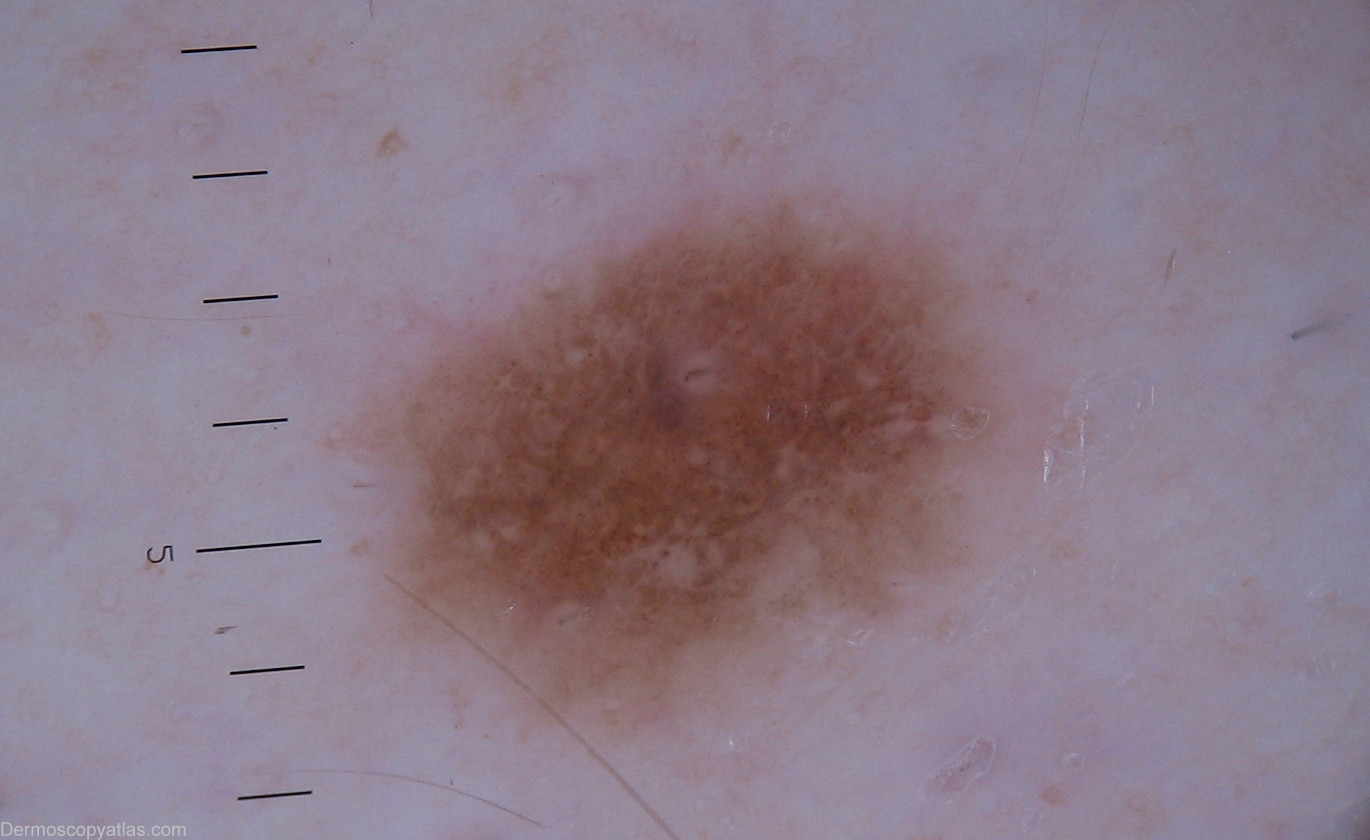

Diagnosis - Nevus dysplastic